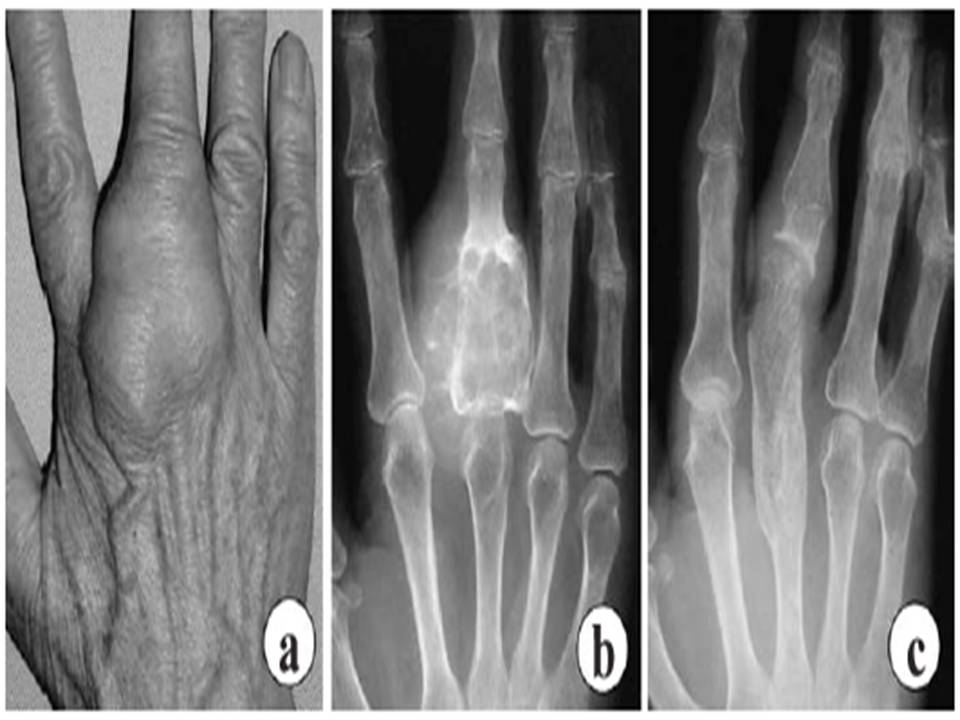

a. Proximal phalanx of the middle finger is swollen. b. Expanding radiolucent mass in the proximal phalangeal bone. c. No recurrence was seen even 3 years after treatment.